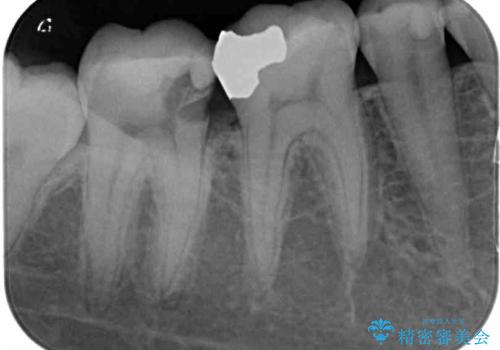

- 右上下の奥歯がむし歯でしみたり痛んだりするとのことで来院された患者様です。

下顎の奥歯は強い痛みを感じており、既に歯髄に不可逆的な炎症が起きていると診断されたため、根管治療の後にセラミッククラウンにて補綴治療を行うこととしました。

上顎の奥歯は最近銀歯による治療を行ったとのことでしたが、適合が不十分であり隙間からしみていたため、適合の良いゴールドインレーにて修復治療を行うこととしました。

下顎のむし歯は歯肉の中にまで及んでいたため、一部歯槽骨を削除し、歯肉縁上に健全歯質が位置するよう外科処置を併用しました。